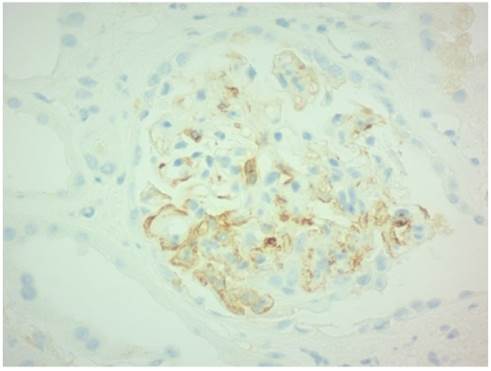

De acuerdo con la clasificación de Oxford, en el 50 % del total de las biopsias renales se encontró hipercelularidad mesangial, seguido por hipercelularidad endocapilar (26.6 %), el 42.9 % mostró glomeruloesclerosis focal y segmentaria, y el 14.2 % fibrosis intersticial y atrofia tubular (IFTA) T1-T2 (tabla 3). Se encontraron dos biopsias con tinción positiva para C4d, una con localización focal en paredes glomerulares y la otra difusa en el área mesangial y paredes glomerulares (figura 2).

En nuestro estudio no se encontraron variables clínicas, ni histológicas, de peor pronóstico renal en los pacientes con NIgA y tinción para C4d positiva en biopsia renal. Encontramos que el 14.2 % de los participantes tuvo una tinción positiva para C4d en la biopsia renal, lo cual es un porcentaje menor del reportado en otros estudios [17,18, 23, 26, 28]. En nuestro estudio, uno de ellos, al momento del diagnóstico, tuvo proteinuria leve y una TFG de 117 mL/min/1.73m2. Al final del seguimiento de este caso no se evidenció deterioro de la función renal (123 mL/min/1.73m2). En la biopsia se reportó C4d focal en paredes glomerulares, sin glomeruloesclerosis global ni focal y segmentaria, sin semilunas fibrosas ni celulares, ausencia de hipercelularidad mesangial y endocapilar, e IFTA 0-25 % (T0). En el segundo caso no se contó con datos clínicos debido a pérdida en su seguimiento. La biopsia de este caso reportó una tinción difusa para C4d en el área mesangial y las paredes glomerulares.